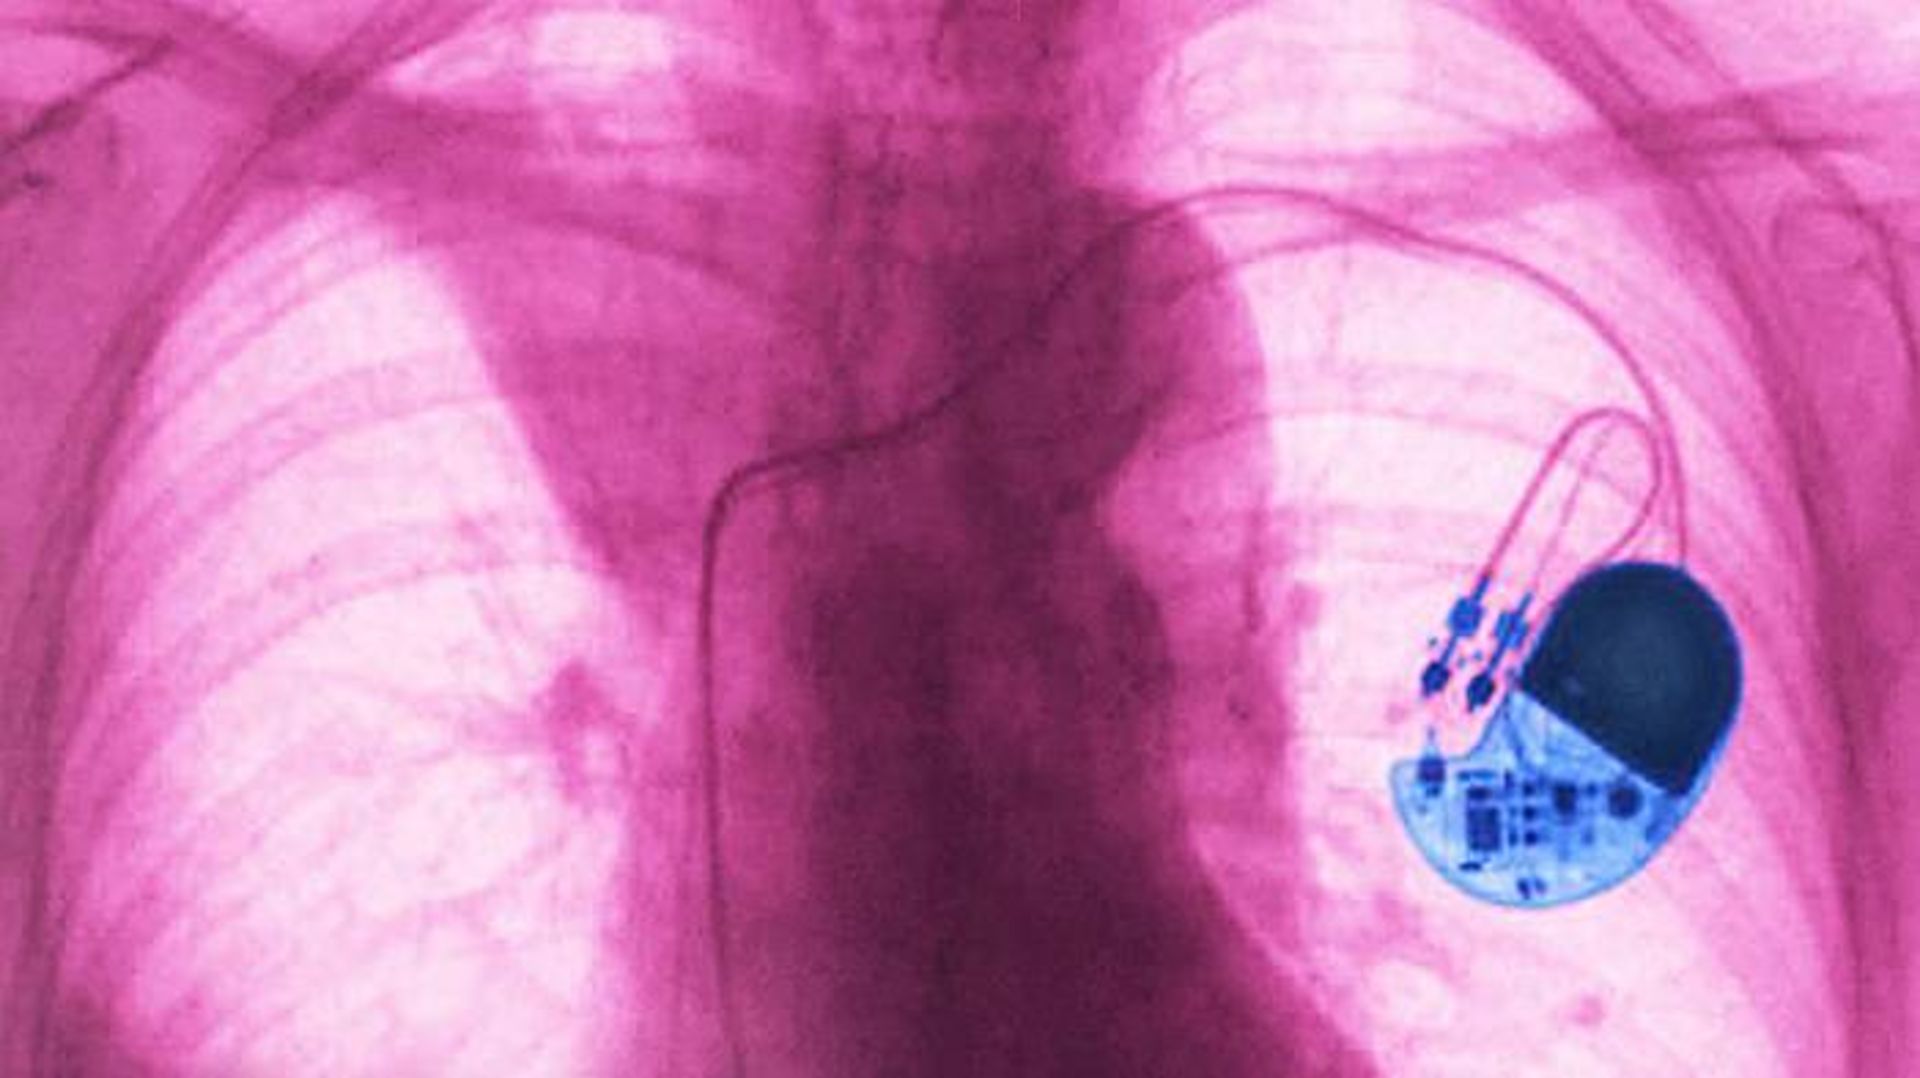

ضربان‌ساز مدرن یکی از شگفتی‌های علم پزشکی است. این دستگاه کاشتنی که اندازه‌ی آن بیشتر از یک قوطی کبریت نیست، پالس‌های الکتریکی را به قلب انسان ارسال می‌کند تا ضربان قلب او منظم بماند. در سرتاسر جهان، هرساله ۱/۲۵ میلیون بیمار مجهز به ضربان‌ساز می‌شوند. این دستگاه کیفیت زندگی بیمارانی را که ضربان قلب آن‌ها غیرطبیعی است، بهبود می‌بخشد و امید به زندگی برخی افراد را به سطح عادی بازمی‌گرداند.

درحالی‌که دستگاه‌های فیزیکی به‌تدریج طی چند دهه‌ی گذشته و پس از زمانی که نخستن ضربان‌ساز کاملا قابل کاشت در سال ۱۹۵۸ به کار گرفته شد، بهبود پیدا کرده است، ایده‌ی اصلی ضربان‌ساز تغییری نکرده است. الکترودهای کاشته‌شده، ضربان قلب شما را تحت نظارت قرار می‌دهند و اگر غیرطبیعی شود، دستگاه می‌تواند پالس‌های الکتریکی را ارسال کند تا ماهیچه‌های قلب منقبض شده و قلب همچنان بتواند خون را به سرتاسر بدن پمپاژ کنند. چه هنگام خواب و چه در جریان فعالیت بدنی، ضربان‌ساز باید قلب را در وضعیتی نگه دارد که با همان ریتم مطمئن بزند.

ضربان ساز

پژوهشگران امیدوارند با تلفیق هوش مصنوعی در ضربان‌سازها، این دستگاه‌ها عملکردهای دیگری به‌جز حفظ ضربان قلب به دست آورند